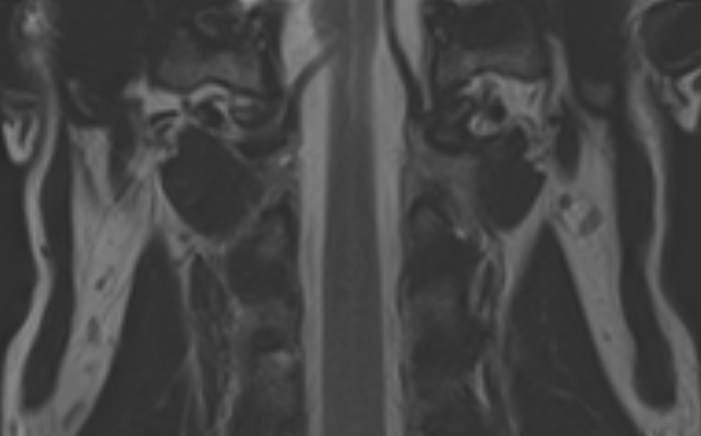

Магнитно-резонансная томография показывает состояние позвонков и связок краниовертебрального отдела, в том числе последствия застарелых травм. А также отклонения в строении:

Краниовертебральный переход − это место соединения черепа с шейным отделом позвоночника. МРТ краниовертебрального перехода делают с целью изучения всех его структур:

Краниовертебральные аномалии (КВА) представляют собой нарушения анатомического взаиморасположения структур позвоночника и черепной коробки. Часто эти патологии протекают бессимптомно, и человек может жить годами, не догадываясь о сбоях в работе организма. Со временем болезнь переходит в хроническую стадию и провоцирует поражения позвоночной артерии, сдавление ствола или корешка спинного мозга, повышение внутричерепного давления. Особенно опасны отклонения в устройстве краниовертебрального перехода у маленьких детей, у которых они могут вызвать расстройства дыхания.Краниовертебральный переход состоит из основания черепа и первых 2 шейных позвонков. Нарушения правильности его строения негативно отражается на работе головного и спинного мозга, что приводит к неврологическим проблемам. Очень важно вовремя выявить патологии зоны соединения позвоночного столба и неподвижной части черепа, если пациенту предстоит мануальная терапия или оперативное вмешательство.В этом случае показана МРТ зоны краниовертебрального перехода, которая основана на принципе использования высокочастотного магнитного поля и радиочастотных импульсов. На данный момент это наиболее информативный и безопасный метод диагностики. Он отличается неинвазивностью и отсутствием лучевой нагрузки, и при этом позволяет получать детализированные трехмерные снимки изучаемой области.